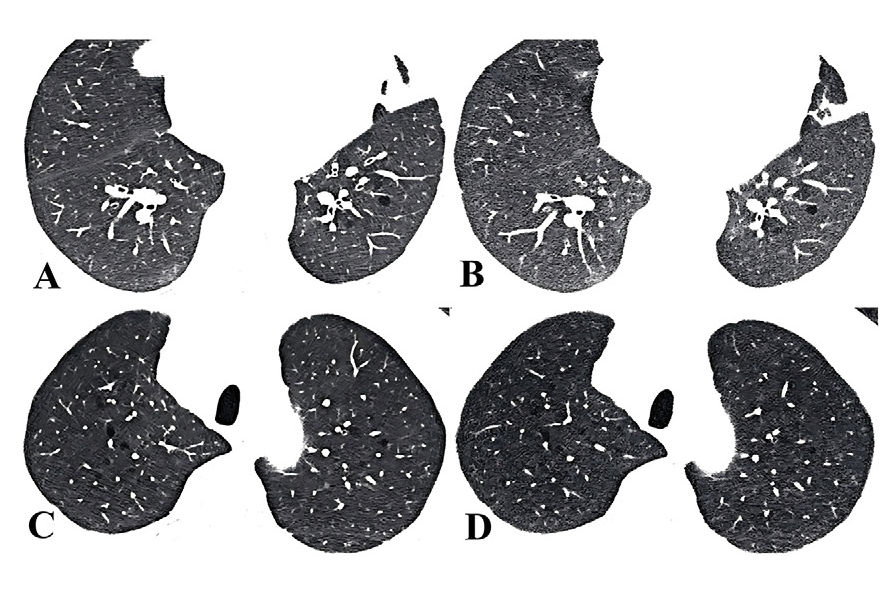

| Virtual endoscopic image at screening CTC shows a flat colon polyp, which was confirmed on optic colonoscopy. Image courtesy of Dr. Takashi Sakamoto. |